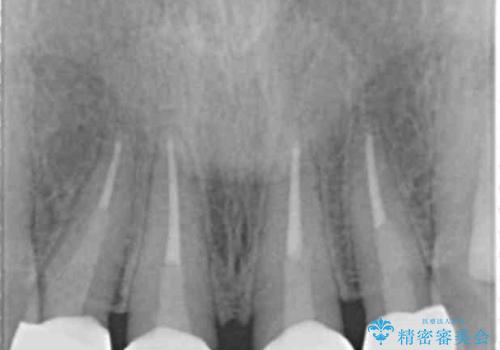

レントゲンを撮影したところ土台の植立も不十分であったため、土台からやりかえることにしました。

自然な仕上がりに大変喜んで頂けました。

単冠かつ適合の良いクラウンにより清掃性が良くなり、歯茎の腫れ・出血もなくなりました。

天然歯と見紛うほど自然なセラミッククラウンは、熟練した技工士さんの技術の賜物です。

クラウンの種類:ジルコニアオールセラミッククラウン エクセレント